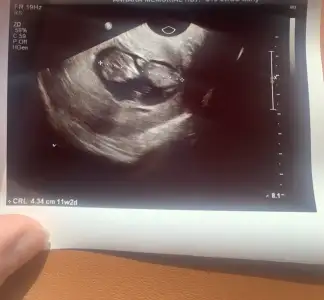

Benim de bugün kontrolüm vardı kızlar, normalde 10+4 ama 11+2 çıktı bebik. Tahmin sorucam ama poposunu dönmüş 😅

Doktorum bir dahaki randevuyu 15 hazirana verdi, nifty testini de ogün konuşacakmışız. Bu durumda 13 haftalık olmuş olacağız. Bir sorun çıkması, kaybetme ihtimali beni çok korkutuyor, umarım stresim bebeğe yansımıyordur. Belki arada devlet hastanesine giderim perinatolojiye.

• IMG_4362.webp

IMG_4362.webp

34,6 KB · Görüntüleme: 73